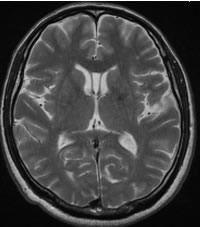

| T2強調画像(ティーツー) | 主に水分を白く、血流を黒く表す撮り方 |